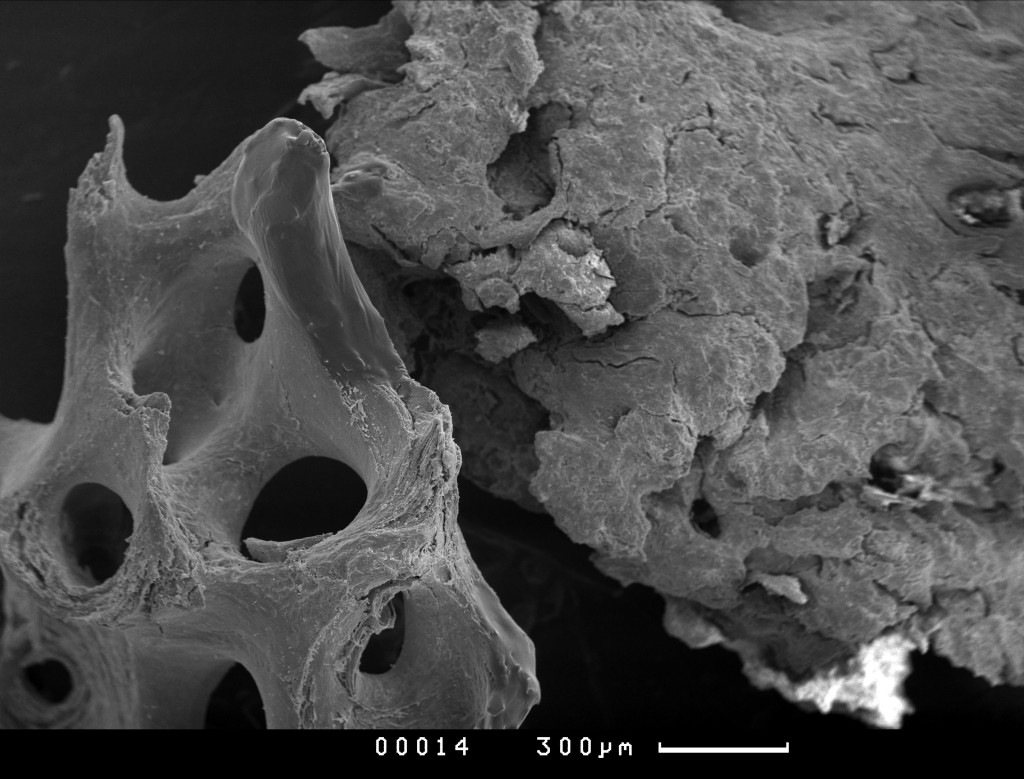

Материал БИОИМПЛАНТ ГАП - это 100% гидроксиаппатит в виде крошки или чипсов. Он представляет собой минеральный матрикс кости с сохраненной природной архитектоникой при полном отсутствии всех органических составляющих костной ткани. В отличие от синтетических материалов данный минеральный матрикс по химическому, морфологическому и структурному составу практически идентичен минеральному матриксу в кости человека. Выраженная топографическая шероховатость и хорошая пористость материала БИОИМПЛАНТ ГАП способствует более лучшей его фиксации и обеспечению размножения остеобластов, а также способствует миграции остеоцитов и ремодуляции костной ткани.

Чипсы Биоимплант ГАП после 1000гр Микросъемка производилась на СЭМ “CamScan S-4” фирмы Cambridge Instruments , Англия. Ускоряющее напряжение 20 кВ, режим регистрации вторичных электронов.

Чипсы Биоимплант ГАП после 1000гр Условия подготовки образцов и микросъемки в сканирующем электронном микроскопе (СЭМ)

Природная архитектоника материала БИОИМПЛАНТ ГАП представляет собой оптимальный каркас для прорастания кровеносных сосудов и глубокого проникновения клеток организма, участвующих в процессах остеосинтеза. Большая площадь поверхности и шероховатость материала БИОИМПЛАНТ ГАП обуславливает его высокую гидрофильность и, как следствие этого, приводит к быстрому впитыванию различных тканевых белков и крови , а также миграции в него клеток организма. Капиллярный эффект проникновения для любых жидкостей и клеток делает материал БИОИМПЛАНТ ГАП надежным и предсказуемым материалом в повседневной клинической практике.